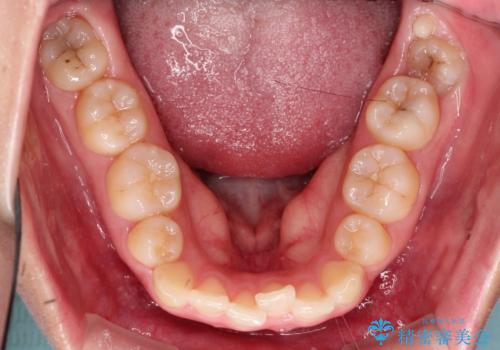

奥歯の噛み合わせは綺麗に噛んでいたため、前歯の叢生(でこぼこ)を、短期間で治療完了するように計画しました。

前歯のガタツキを改善する治療法として、マウスピース矯正が適していることが多いです。

マウスピース矯正は、金属製のブラケットやワイヤーを使用せずに、透明なマウスピースを装着して歯を移動させる方法です。そのため、目立たず、痛みも少ないです。